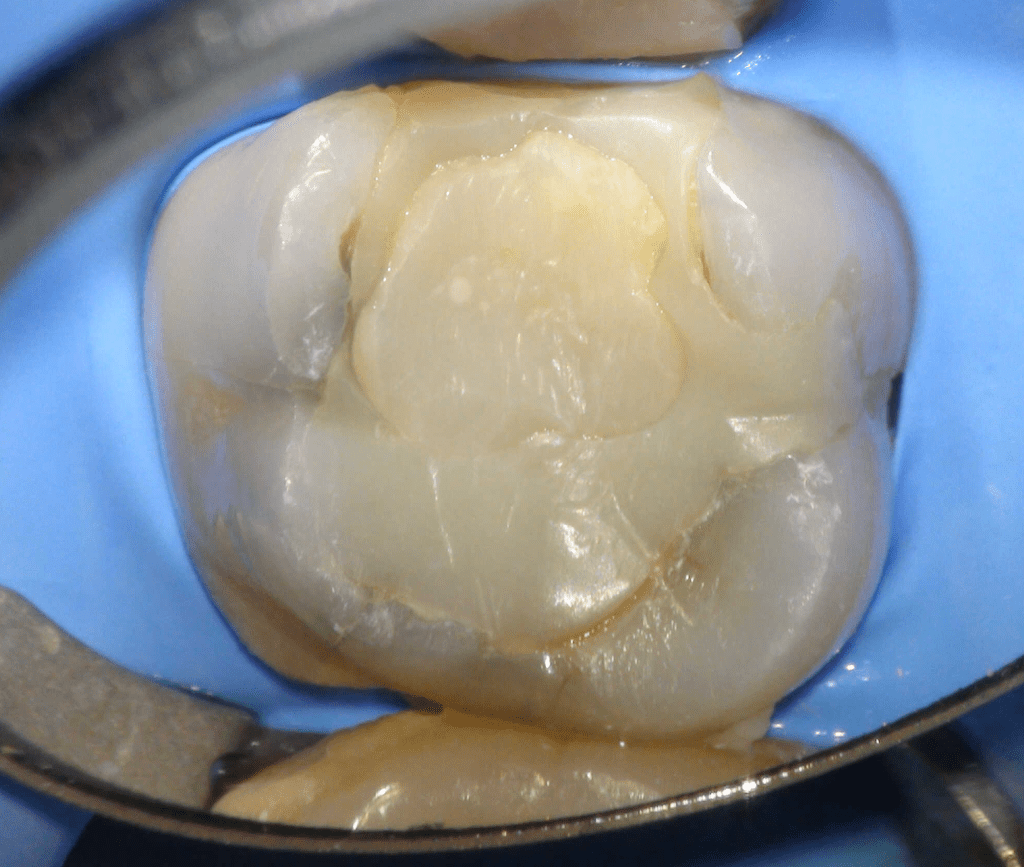

Pulpotomía biodentine + reco preendio